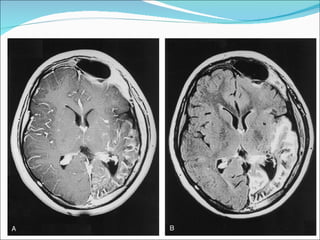

1) O documento descreve o Síndrome de Sturge-Weber, uma condição neurocutânea não hereditária caracterizada por nevo facial e convulsões. 2) O Angioma Cutâneo de Sturge-Weber aparece na área de inervação do trigêmeo, enquanto o Angioma Leptomeningeal aparece nos sulcos corticais parietais e occipitais. 3) Os achados de imagem incluem realce no espaço subaracnóideo e hipersinal na substância branca adjac